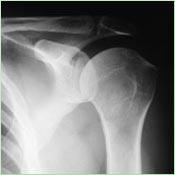

Skiagrafický snímek ramene

Skiagrafický snímek ramene.

Skiagrafie

Skiagrafie je technika zobrazení lidských tkání, využívající rozdílnou hodnotu pohlcení procházejícího svazku rentgenového záření v různých tkáních. Výsledkem je obraz zachycený na citlivý materiál - rentgenový film či detekční systém přístroje. Ze získaného obrazu pak lze vyhodnotit vnitřní stavbu vyšetřovaného orgánu a jeho případné patologické stavy. Rentgenové vyšetření se hodí zejména k vyšetřování kostí, kloubů, páteře, plic, ale lze zobrazit i měkké tkáně.